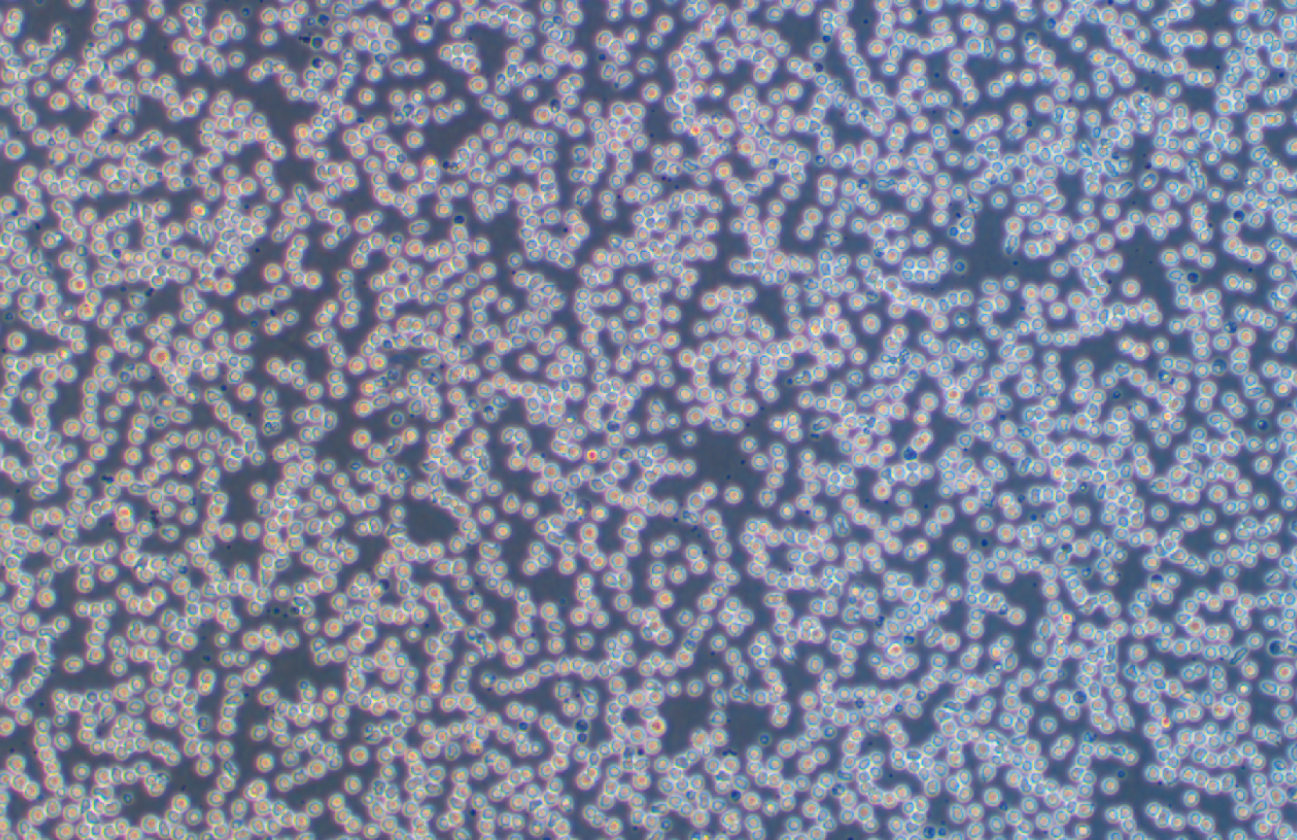

形態 |

淋巴母細胞樣 |

生長特征 |

懸浮生長 |